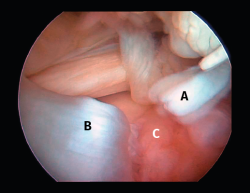

Figura 2. Rotura del manguito rotador en forma de U. A: tendón infraespinoso; B: tendón supraespinoso; C: cabeza humeral.

Figura 5. Rotura de tipo C1. A: rotura pequeña de espesor completo del supraespinoso; B: cabeza humeral.

Sin embargo, las clasificaciones basadas en el tamaño de la rotura deben ser bidimensionales, ya que la visión unidimensional puede ser engañosa, al mostrar el tamaño de la rotura solo desde el plano anteroposterior(4). Por esta razón, proponemos el sistema de clasificación del manguito posterosuperior sugerida por Snyder, que aporta información no solo del tamaño, sino del número de tendones afectados y la presencia de tejido cicatricial(7). En las lesiones de tipo C1 la lesión atraviesa todo el espesor del tendón y en el eje transversal es pequeña y punzante (Figura 5). Las de tipo C2 son roturas de espesor completo pero la distancia entre los extremos de la rotura es menor de 2 cm con escasa retracción (Figura 6). En las de tipo C3 la rotura afecta en sentido transversal entre 3 y 4 cm con mayor retracción implicando 2 tendones (Figura 7). Y las de tipo C4 son la rotura masiva del manguito de los rotadores con una afectación de espesor completo de toda la anchura de 2 o más tendones asociando importante retracción (Figura 8).